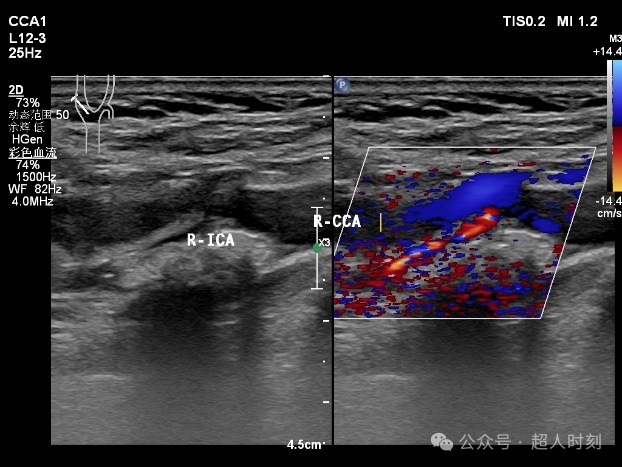

患者,男性,78岁,因“反复头痛头晕‚伴右眼黑朦1+年,肢体麻木偶感上肢无力6+月”入院。颈动脉彩超:右颈内动脉明显狭窄(狭窄率70%-99%),双侧颈总动脉多处狭窄(狭窄率<50%)。TCCD:颅内多支动脉狭窄(见图5)。

图5a 右颈内动脉颈段粥样斑块伴狭窄